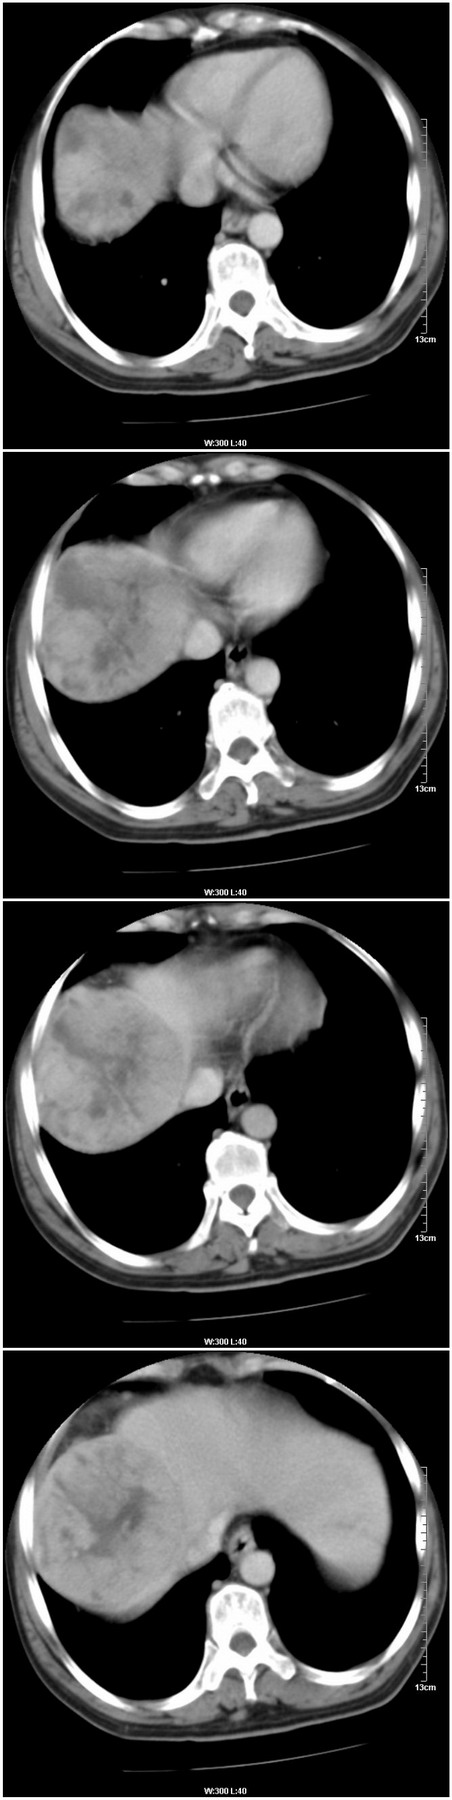

标题: [肝脏占位]CT13576:男性,57岁。胸腹痛伴消瘦半年余。 [打印本页]

标题: [肝脏占位]CT13576:男性,57岁。胸腹痛伴消瘦半年余。

增强情况:

病灶密度变化 正常肝组织密度变化

平扫病灶平均ct值:51.3hu 56hu

动脉期: 74.2hu 69hu

门脉期: 85.9hu 102 hu

4分钟后: 71.8hu 76hu

9分钟后: 71.9hu 72.9hu

这是又一例门脉期强化比动脉期强化明显的病例。往常我们所见到的都是由于肝癌是动脉供血,所以病变常在动脉期明显强化,而在门脉期就会下降。但是这一例和过去做过的一个病例都是在门脉期更明显强化,请战友们分析这种变化的实质。有人提出这是正常肝组织逐渐向肝癌转化的一个过程,也有人说这是另一种肝癌的类型,就是相对于一动脉供血为主的肝癌来说,这是一种以门脉供血为主的一种肝癌类型。战友们说说看,你认为怎样解释这种情况更合适呢?

1.肝右叶巨块性病变,周围有假包膜,内部密度不均,有坏死,增强后以门脉期强化明显,反应以门脉供血的特征,为不典型肝癌(梁索性)。

2.双肾及输尿管结石。

考虑 1、肝右叶巨块型肝癌;

2、双肾及输尿管结石。